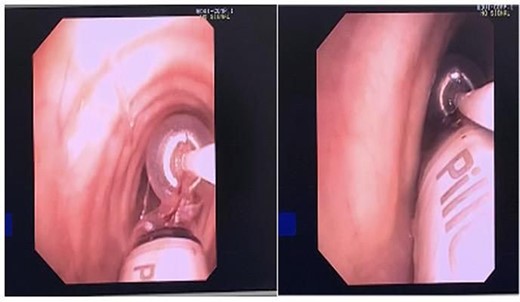

Post review, the patient consented to rigid/flexible bronchoscopy and retrieval of a foreign body. Because of the prevalent coronavirus disease 2019 (COVID-19) pandemic, the procedure was performed with full COVID precautions. A flexible bronchoscope evaluation was performed with the patient under general anaesthesia and through a size 8.5 endotracheal tube (ETT). The capsule was found to be lodged in the bronchus intermedius (Fig. 1B). The size of the capsule (26.2 × 11.4 mm) and its very smooth surface meant that it could not be grasped by available endobronchial instruments. Attempts to trap it in a Nitnol tipless stone extractor basket (2.2 cm) were not successful. We subsequently tried using Fogarty catheters (of sizes 3–7). Although we were able to dislodge the capsule into the trachea, the size discrepancy between the balloon and trachea and perhaps because of the weight of the capsule, it could not be delivered into the upper trachea it repeatedly slipped back to the bronchus on the right. Because of this repeated slippage, the patient was placed in a stip Trendelenburg position. The use of gravity prevented slippage of the capsule distally. After this manoeuvre, the capsule was drawn to the tip of the ETT. The capsule was wedged between the balloon of the Fogarty and the ETT tip and they were all withdrawn as a unit (Fig. 2). The capsule was brought outside the vocal cords and retrieved using Magill forceps. The patient was subsequently reintubated until subsequent extubation. The postoperative recovery was uneventful.

An advertent aspiration is a known complication of capsule endoscopy occurring about 1/1000 cases [4] and has the potential to lead to a significant clinical problem especially in the elderly [5]. The size and the smoothness of the capsule makes extraction difficult and conventional grasping forceps are not usually successful. A variety of endobronchial tools have been used including snares [4], Roth Net retrieval device, stone basket, Roth Net expandable foreign body extractor, Fogarty Balloon catheter, rat-toothed graspers through flexible or rigid bronchoscope [6] have been described. In our case, despite the use of available devices, extraction proved difficult. Success was only attained after patient was put in Trendelenburg position and the capsule was wedged between the balloon of the Fogarty and the tip of ETT. This manoeuvre though successful does require help and co-ordination of the entire theatre team to ensure patient remains secure on the operating table.